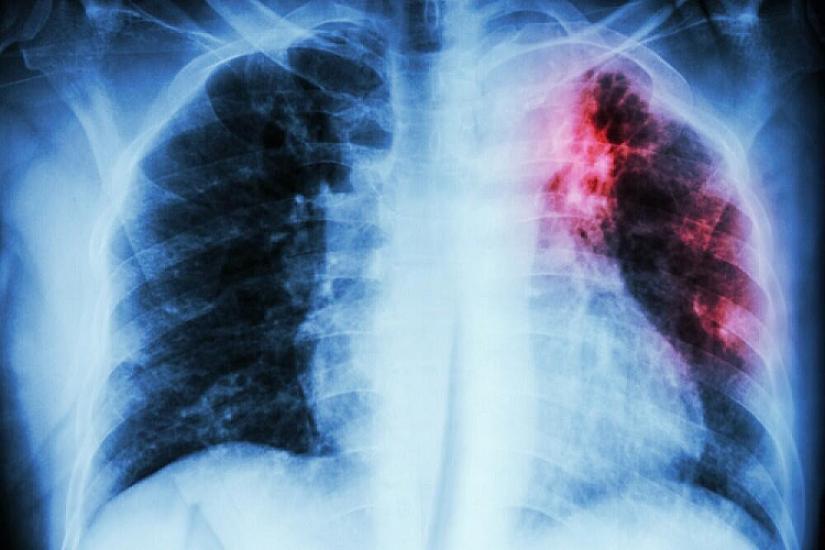

The dynamics of tuberculosis incidence in Azerbaijan (per 100,000 population): this indicator was 41.1 in 2015, while in 2025 it was recorded as 21.5.

In Azerbaijan, the dynamics of detection of MDR-TB (Multidrug-Resistant Mycobacterium tuberculosis) among new pulmonary tuberculosis patients was 53% in 2015, while in 2025 this indicator reached 86%.

"The treatment outcomes for both drug-sensitive and drug-resistant patients have been higher. The tuberculosis incidence rates among children and adolescents have significantly improved. While in 2015 there were 369 children and adolescents diagnosed with tuberculosis in the country, in 2025 the number of sick children and adolescents was 198. Even for 2024, this indicator was 278, which is evidence of a significant change."